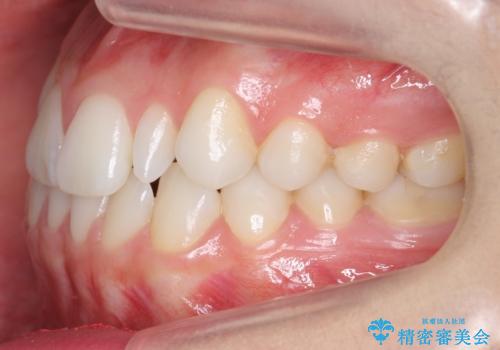

- 前歯のがたつきと小さな歯の形を治したいと来院。

前から2番目の歯が小さく、細くとがった形になっていました。

大きくしようにも、幅が少ない上に、また、内側に入ってしまっているため、矯正治療で前歯を並べてからセラミックでかぶせることにしました。

いきなりセラミックでかぶせるよりも手間をかけた分、自然な仕上がりになっています。

先に矯正治療をすることで、下の前歯を内側に入れることができ、上の歯のセラミックの幅や厚みを取ることができました。